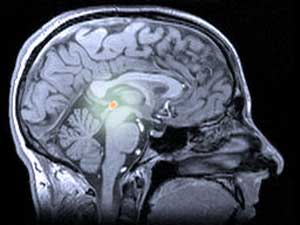

Negli esseri umani e in altri animali, la melatonina è prodotta dalla ghiandola pineale (pronunciata ‘pie-kneel’), una struttura leggermente misteriosa situata in profondità nel cervello. La ghiandola pineale viene talvolta definita ‘terzo occhio’, perché in alcune lucertole si trova sulla sommità della testa e viene utilizzata per rilevare le ombre dei predatori volanti.

La luce e il buio sono importanti anche per la ghiandola pineale umana e per la melatonina che produce. La ghiandola pineale riceve segnali luminosi dagli occhi e rilascia melatonina quando è buio. La melatonina agisce sui centri del sonno del cervello e ci rende assonnati. A lungo termine, il calo giornaliero e l’aumento notturno della melatonina regolano il nostro schema di sonno e veglia, mantenendolo sincronizzato con i cambiamenti della luce del giorno.